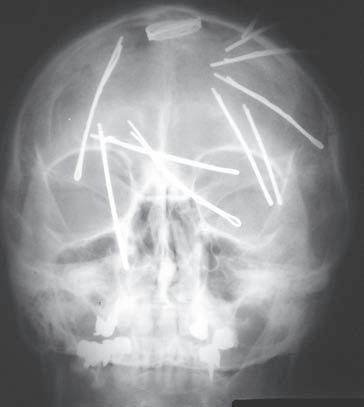

O br. 1. 1 Princip d vou proje k cí. S k iagram l e bk y v pře d oza d ní proje k ci (a). Spon k y do vlasů ne j sou lokalizovány intrakraniálně, ale na temeni ve vlasech, j ak j e zře j mé ze skiagramu lebky v boční projekci (b)